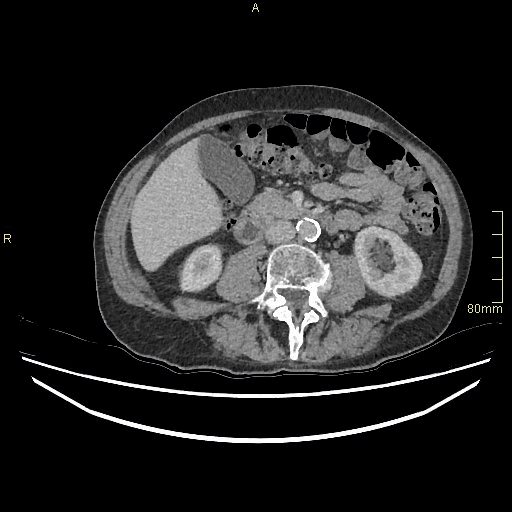

CT Pelvis (Portal Venous Axial)